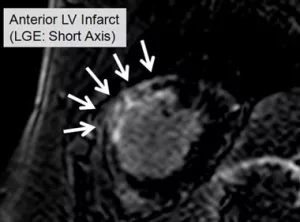

MRI/3D-STE